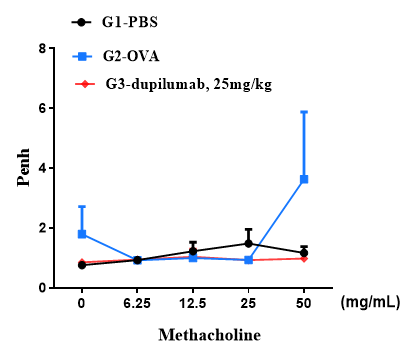

Airway responses following the exposure to increasing doses of methacholine (MCh) were measured for each mouse 24h after the final allergen or PBS exposure using the whole-body plethysmography. The y-axis represents the Penh absolute value. Increasing doses of methacholine were administered by aerosols.

B-hIL4/hIL4RA mice (C57BL/6)